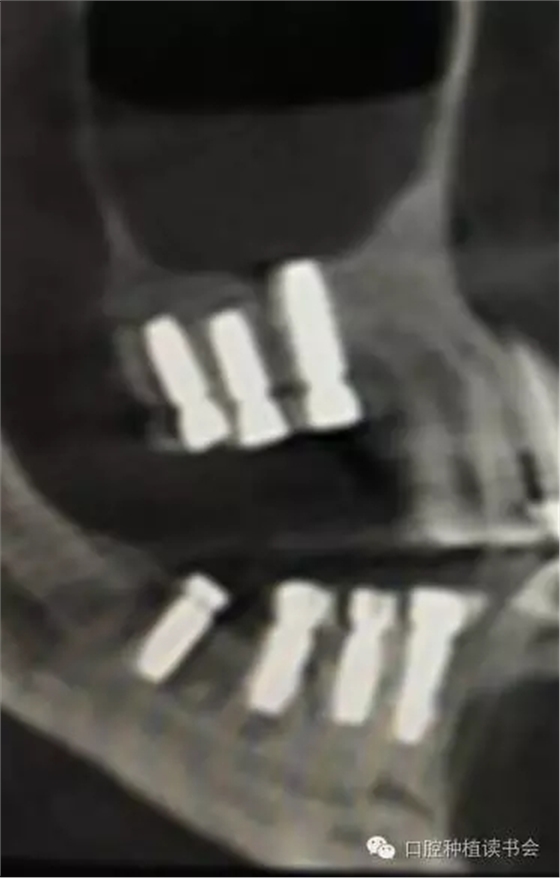

除了諸多解剖因素和生理病理因素,是否選擇上頜竇提升術(shù)(尤其是側(cè)壁開(kāi)窗術(shù))或判斷術(shù)后預(yù)期,與病人是否有基礎(chǔ)病(如糖尿病)、病人是否經(jīng)過(guò)頭部放療、是否因骨質(zhì)疏松而長(zhǎng)期服用雙膦酸鹽類藥物等相關(guān)因素均緊密相關(guān)。根據(jù)上頜竇的解剖特點(diǎn),在長(zhǎng)期實(shí)踐中,基本形成了2類上頜竇底提升的方法。1、經(jīng)牙槽脊頂提升粘膜的方法稱為內(nèi)提升,具有代表性的技術(shù)是1986年Tatum提出的經(jīng)牙槽脊提升上頜竇技術(shù)和1994年Summers提出利用內(nèi)提升器械自牙槽嵴頂入路的沖頂式上頜竇內(nèi)提升技術(shù)(osteotome sinus floor elevation,OSFE),又稱閉合式提升術(shù) (closed sinus lift technique)。前者通過(guò)牙槽脊頂切口,用特殊的窩洞成型器代替擴(kuò)孔鉆,敲擊使上頜竇底“骨折”,從而完成提升術(shù)。后者是在竇底1-2mm處用提升器進(jìn)行敲擊抬高竇底。其后多年來(lái)人們利用工具的改革創(chuàng)新,使內(nèi)提升技術(shù)有了很大的變革和進(jìn)步,如利用超聲骨刀或其他專用器械去除竇底骨質(zhì),利用球囊等工具以水、氣壓抬高上頜竇粘膜;利用環(huán)鉆進(jìn)行上頜竇底內(nèi)嵌骨塊內(nèi)提升;也有通過(guò)磁力車針進(jìn)行上頜竇底骨質(zhì)預(yù)備,通過(guò)同極排斥的原理,當(dāng)竇底骨質(zhì)去盡后,粘膜被車針“彈升”;也有通過(guò)牙槽脊頂開(kāi)窗植骨的病例報(bào)道(Winter,2003)。因此,隨著上頜竇提升技術(shù)的不斷改進(jìn)、各種新型手術(shù)器械的出現(xiàn),在RBH<4mm的情況下,上頜竇內(nèi)提升的方式也越來(lái)越被大家所采用(Nedir,2009)。2、經(jīng)側(cè)壁開(kāi)窗分離粘膜抬高竇底的方法稱為外提升(Lateral Window Technique)。早期由Philip?Boyne提出,后來(lái)上頜竇側(cè)壁開(kāi)窗在粘膜和竇底之間進(jìn)行骨增量的術(shù)式逐步應(yīng)用開(kāi)來(lái)。側(cè)壁開(kāi)窗后是否同期植入種植體,根據(jù)RBH,種植體穩(wěn)定性的預(yù)判而決定??偟膩?lái)說(shuō),上頜竇外提升術(shù)的成功率86%~100%(Jensen,2009)。根據(jù)CBCT圖像,不但可以提供術(shù)前的種植計(jì)劃指導(dǎo),而且上頜竇外提升術(shù)后的效果,尤其是檢查種植體腭側(cè)是否有植骨不全,都會(huì)一目了然。(圖10-12)